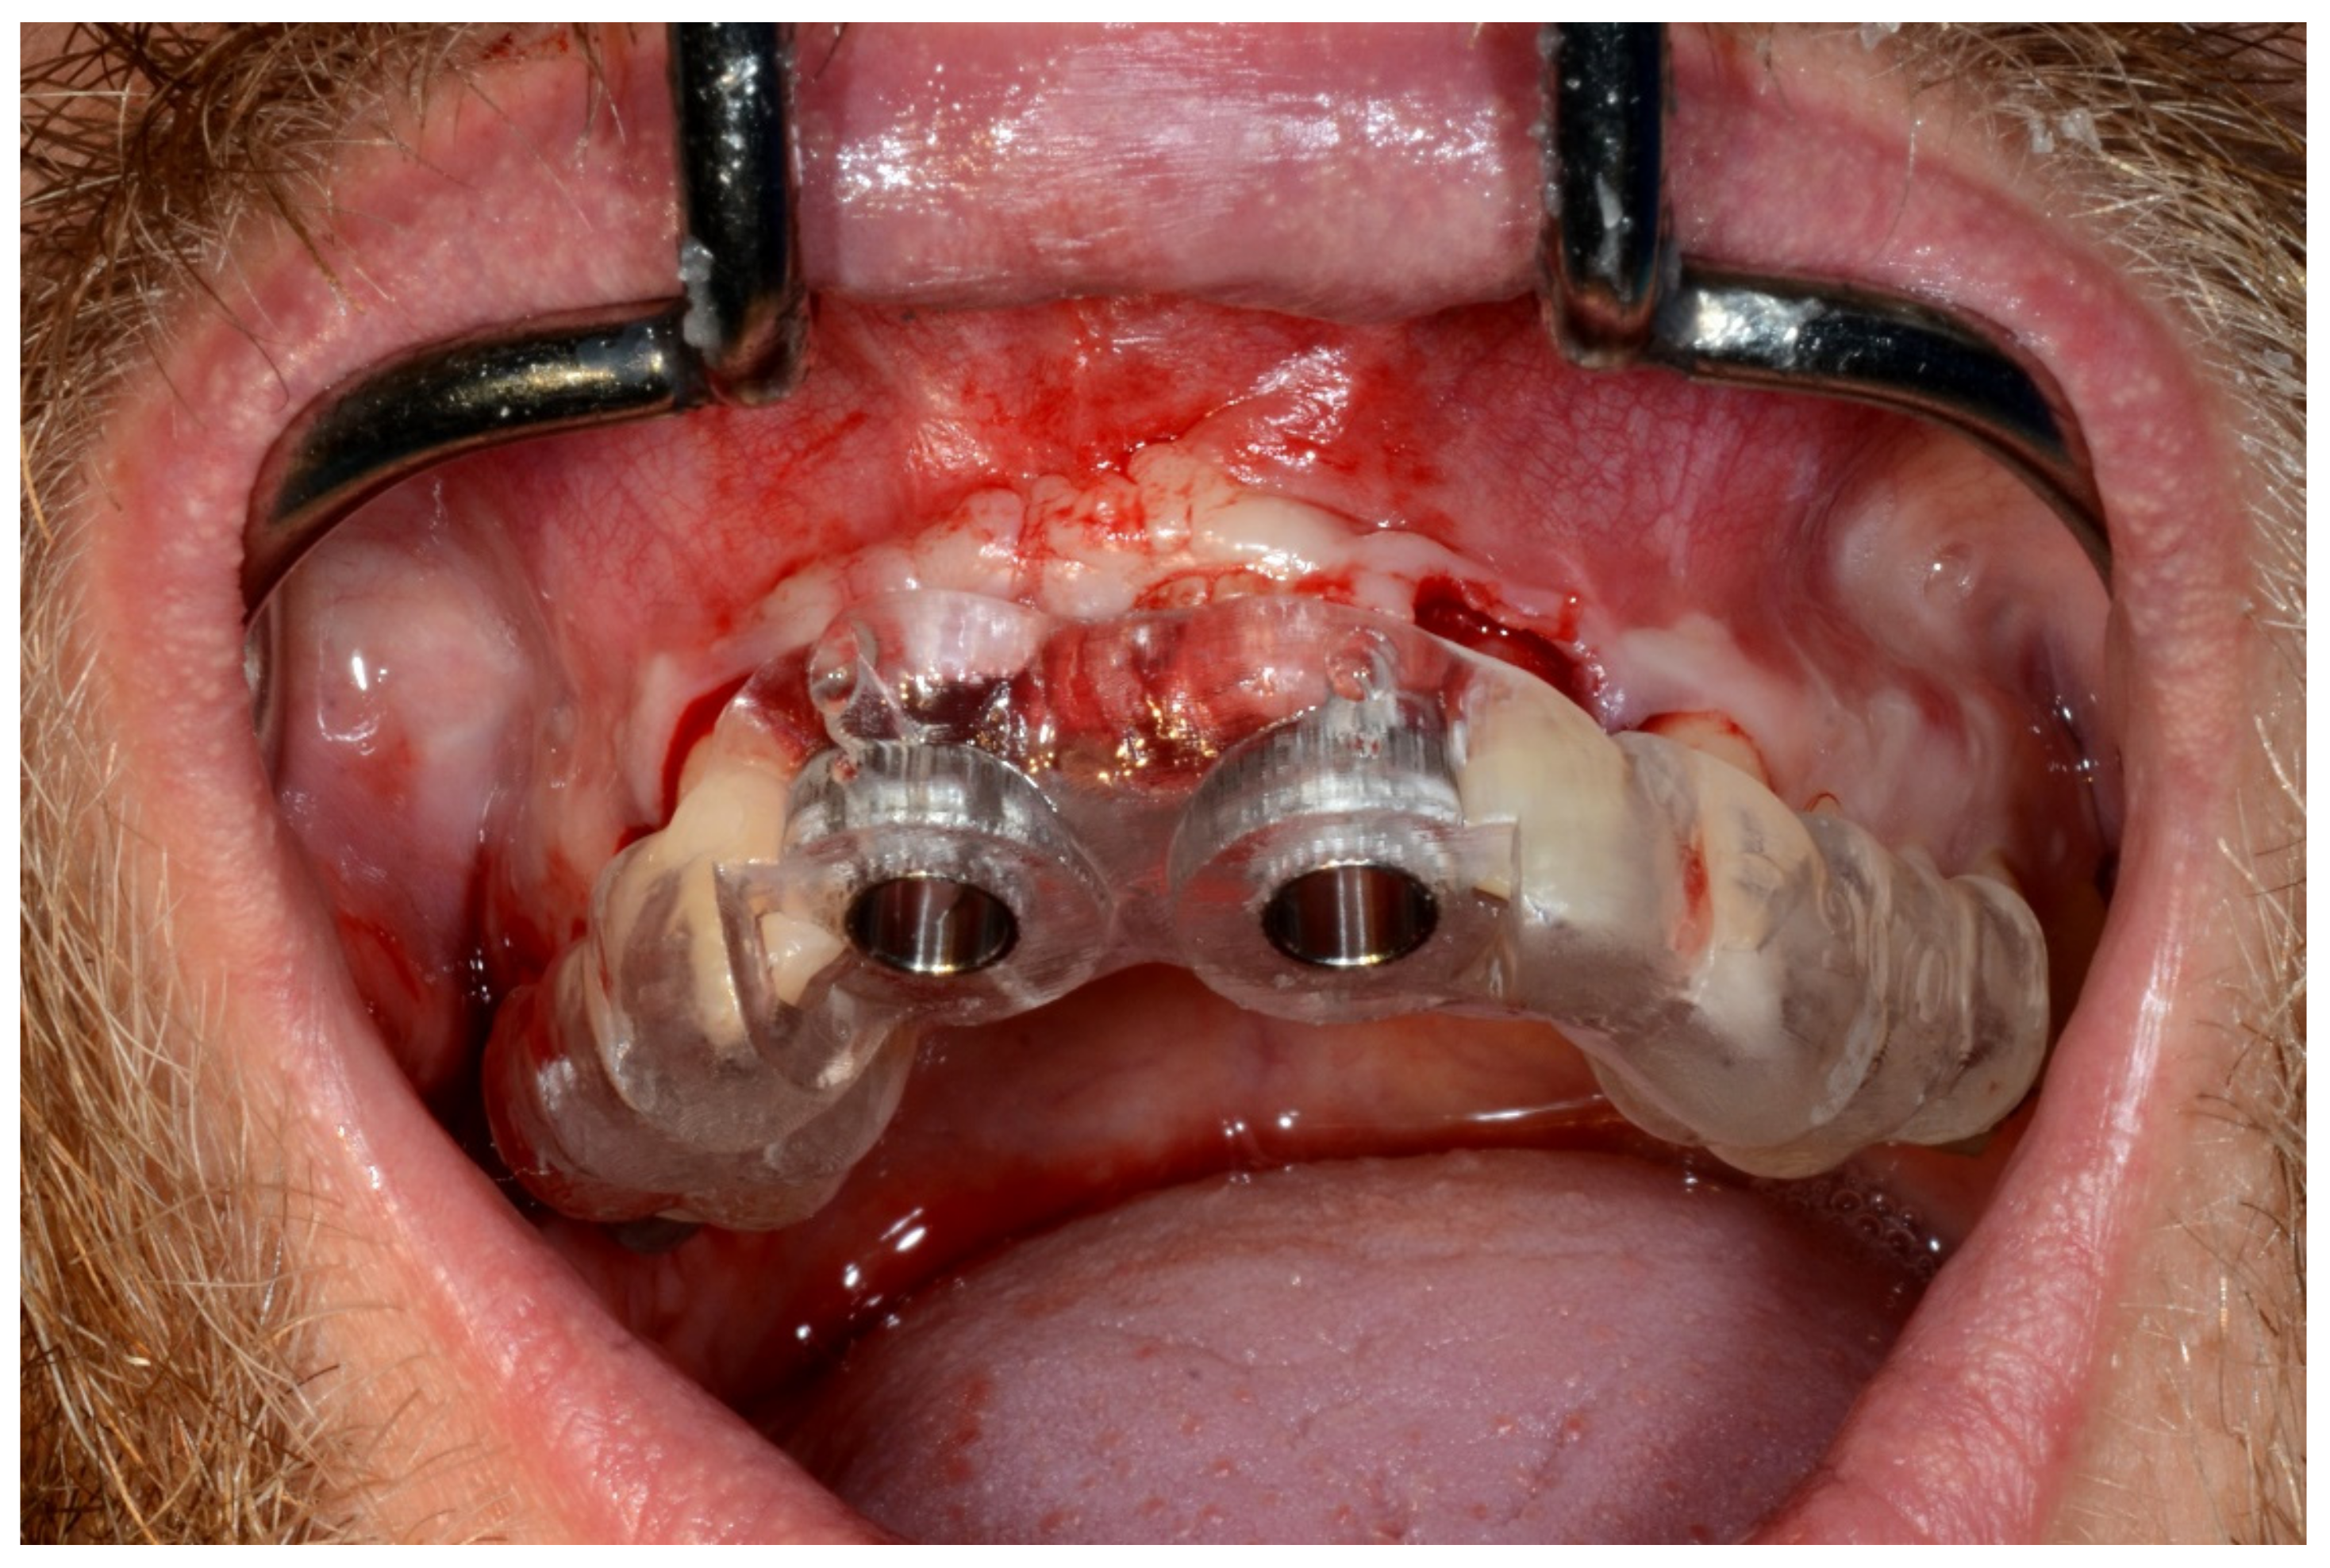

6.2.4. Intra-Operative Documentation:

In March 2013, twelve guided dental implants were placed at sites # 12, # 13, # 15, # 22, # 23, # 25, # 33, # 34, # 36, # 43, # 44, and # 46 (Figure 22, Figure 23, Figure 24, Figure 25 and Figure 26)

Figure 22.

Maxillary surgical drilling guides temporarily supported and fixed with mini-screws.

Figure 23.

Mandibular surgical drilling guides temporarily supported and fixed with mini-screws.

Figure 24.

Implant bed preparation using guided drills inserted into specific ad hoc drill handles.

Figure 25.

Guided implant insertion.